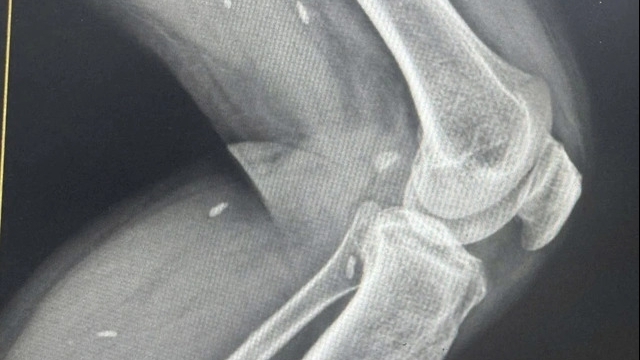

Theo đó, tính riêng trong ngày làm việc đầu tiên đã có gần hơn 100 trẻ đến từ nhiều tỉnh, thành trên cả nước được các chuyên gia của Tổ chức nhân đạo Children Action cùng các bác sĩ Bệnh viện Đa khoa Xanh Pôn trực tiếp khám, sau đó hội chẩn để đưa ra hướng điều trị phù hợp. Kết thúc buổi khám, có trên 30 trẻ được chỉ định phẫu thuật cột sống, bàn chân khoèo, dị tật chi, trật khớp háng bẩm sinh, xương thủy tinh…